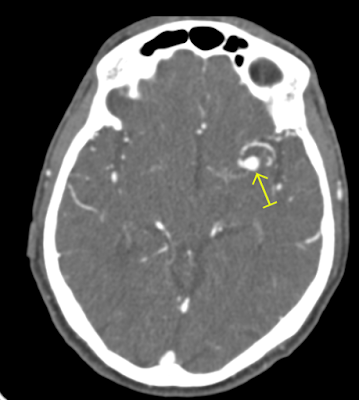

MIP Thin image axial view Aneurysm of opercular segment of left middle cerebral artery.

• Aneurysmal dilatation ( 7.10mm in diameter) is seen in opercular segment of left middle cerebral artery.